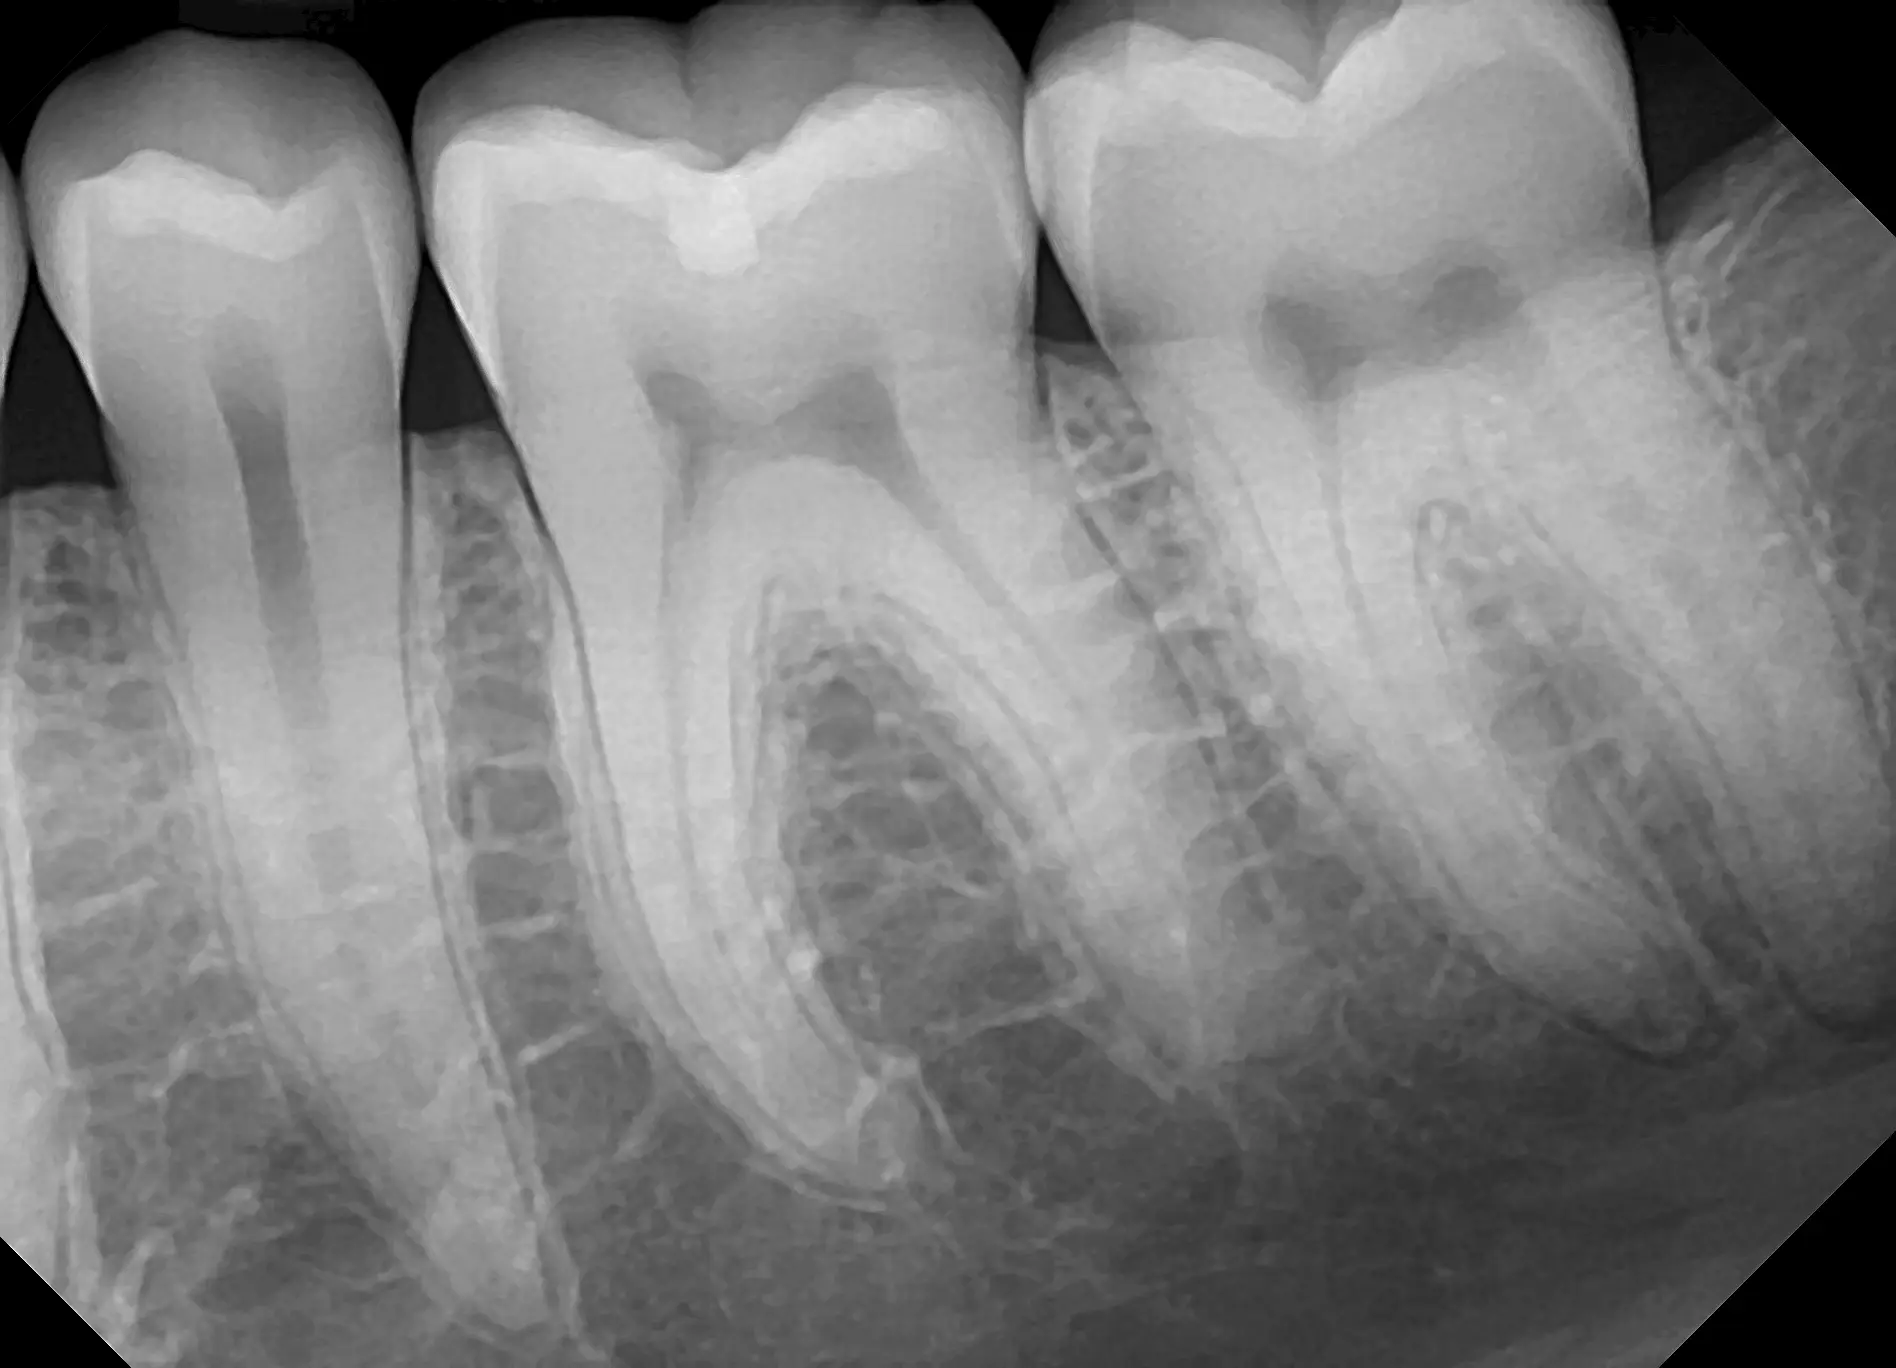

See for yourself the X-ray Gallery from the Dream Sensor!

Click any image in the x-ray gallery below to see the full version.

All images are taken with the DentiMax Dream Sensor and are compatible with the DentiMax Imaging Software and most other imaging software on the market.